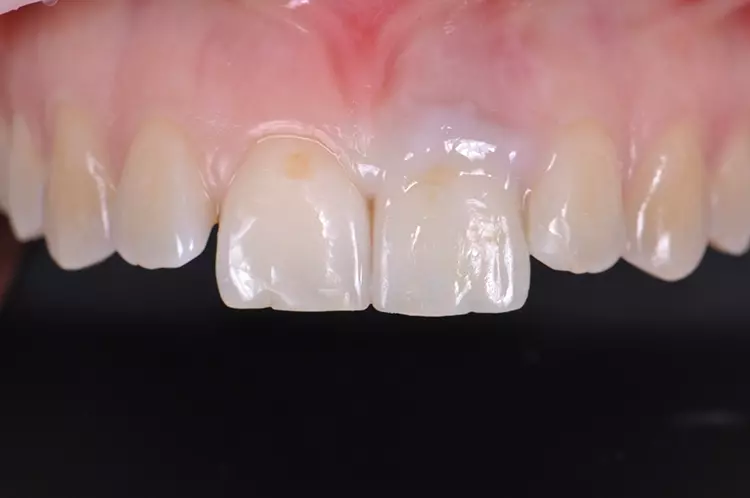

Im Rahmen des Erstgespräches berichtete die junge Patientin von einem Sturzereignis, bei dem der Schneidezahn frakturierte. Ihr damaliger Zahnarzt führte eine Wurzelkanalbehandlung durch und versorgte den Zahn mit einer Krone aus Lithiumdisilikat. Das anfänglich sehr ansprechende ästhetische Behandlungsergebnis hätte sich jedoch nach der Eingliederung mit der Zeit verändert und die Patientin stellte eine zunehmende Verfärbung der Frontzahnkrone fest (Abb. 2 und 3).

Dies kann aus einer nachträglich eingetretenen Verfärbung des devitalen Zahnes resultieren. Durch die sehr hohe Transluzenz der Glasphase einer Lithiumdisilikat-Restauration kann die dunkle Stumpffarbe durchschlagen und zu einem ästhetisch störenden „Grauschleier“ führen. In einem intensiven Beratungs- und Aufklärungsgespräch wurden der Patientin die Schwierigkeiten und Herausforderungen einer Einzelzahnkrone in der ästhetischen Zone bei einer hohen Lachlinie mit Exposition der Gingiva dargestellt.

Manche Details wie die Verfärbung der Gingiva wären nicht korrigierbar und verringerten die Vorhersagbarkeit eines optimalen ästhetischen Resultates. Die Neuversorgung dient der Verbesserung der ästhetischen Situation, eine perfekte Kopie des Zahnes 11 wird nicht zu erzielen sein, da die verfärbte Wurzel bestehen bleibe.

Trotz der aufgeführten Risiken und Unwägbarkeiten wünschte die junge Patientin eine Neuversorgung des Zahnes, um eine bestmögliche Ästhetik zu erreichen. Gleichzeitig sollten ihre natürliche Zahnfarbe und die individuelle Zahnstellung nicht verändert werden.